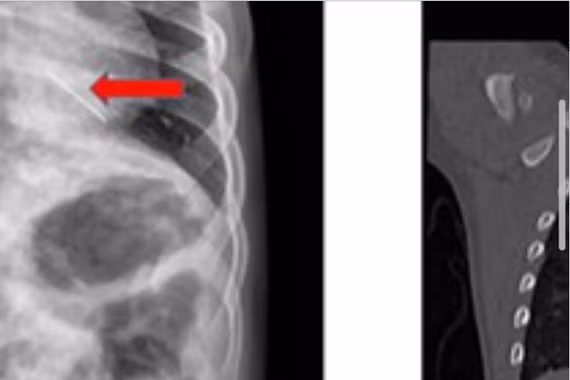

Sau khi đến Trung tâm Y tế khu vực Cẩm Khê thăm khám và thực hiện các xét nghiệm cận lâm sàng, bệnh nhân được chẩn đoán viêm tai giữa mủ nhày bên phải và được điều trị nội khoa theo phác đồ.

Khi tình trạng viêm đã được kiểm soát ổn định, bệnh nhân được chỉ định phẫu thuật tạo hình màng nhĩ bên phải. Sau hội chẩn, các bác sĩ đã lựa chọn phương pháp phẫu thuật nội soi với các ưu điểm nổi trội: Ít xâm lấn; Hạn chế đau; Giảm chảy máu; Thời gian hồi phục nhanh.

Ca phẫu thuật diễn ra thuận lợi. Sau mổ, bệnh nhân tỉnh táo, tiếp xúc tốt và được tiếp tục theo dõi, chăm sóc hậu phẫu. Sau 6 ngày điều trị, tình trạng sức khỏe bệnh nhân ổn định, tiến triển tốt và đã được xuất viện.